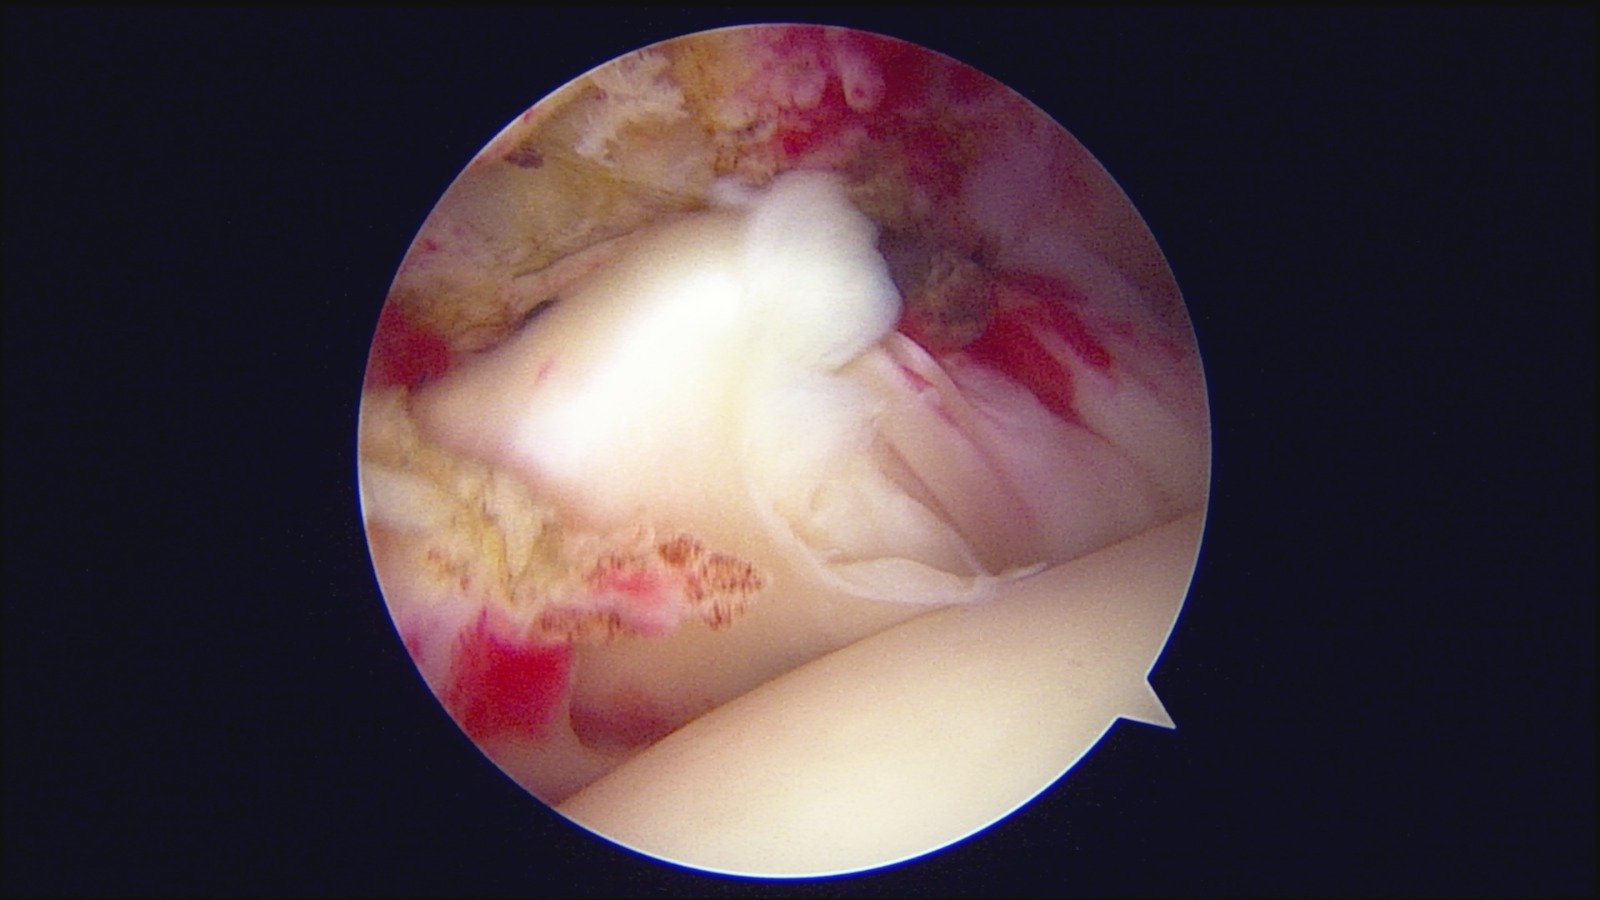

GalleryShoulder rotator cuff repair Meniscus root repair Meniscus repair Bankart repair for recurrent shoulder dislocation ACL reconstruction Machines Instruments